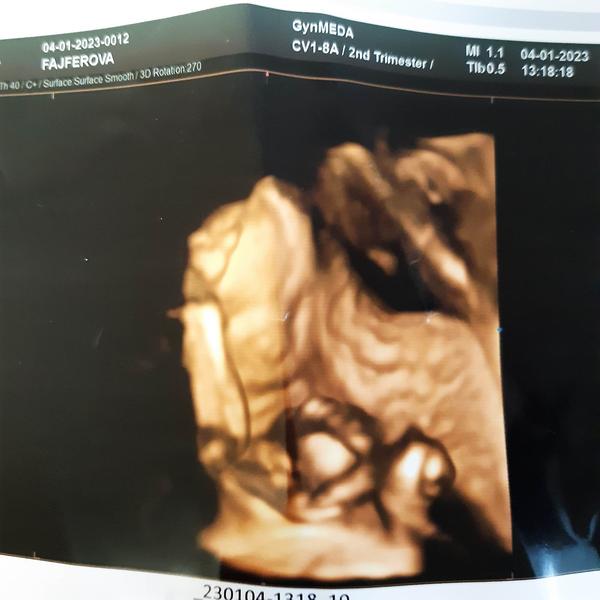

@lucina90 Ahojky holky jj mi to máme stejně na genetice jsme dopadli v pořádku a mrňe se nám do nynějška nechtělo ukázat taky na nás vystrkuje jen zadeček, tak musíme čekat do velkého utz který bude až 9.1 Snad se konečně dovíme jestli holka či kluk 😀